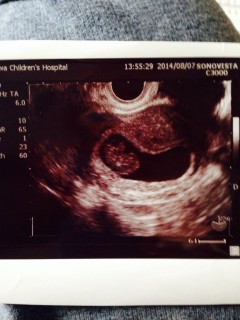

一週間前より頭や手足がはっきりしてきました! 撮影中なかなか動かないな、と先生と画面 ガン見してたら急に頭がピコピコ上下して、 うごうごしてました!可愛いかったです。

特につわりがなくて検診までは無事に育ってくれているのか不安でいっぱいでしたが、ちゃんと二頭身に成長してくれていて安心しました! 大きさは22.9mmで先生にも標準サイズで元気に育ってますねと言われて嬉しかったです☆